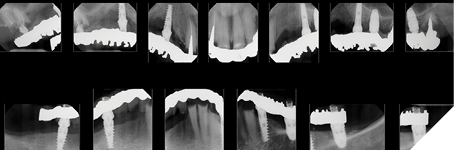

A 55-year-old woman presented with a chief complaint of wanting to complete the treatment of her maxilla and mandible that had begun elsewhere a number of years ago. The patient reported that she had several implants placed and provisional bridges inserted a number of years ago. A review of her medical history revealed no significant findings. A clinical exam was performed, and the following data was collected: a full mouth series radiographic survey, a cone beam CT scan, intraoral surfaces scans, full face and intraoral photos (Figs. 1,2,3).

Fig. 1

Fig. 2

Fig. 3